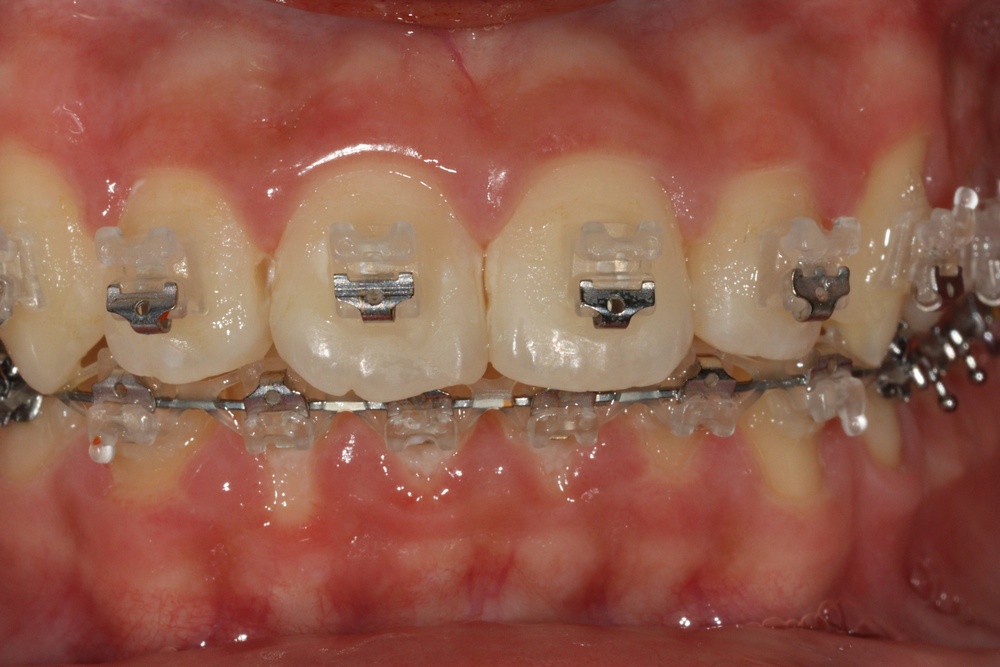

치아 배열이 거의 완성된 상태로 치료 전 말씀드렸던 치아사이의 틈(블랙트라이앵글)이 있습니다.

환자분과 상의 후 위쪽은 벌어진 공간을 레진으로 메꾸기로 하였습니다.